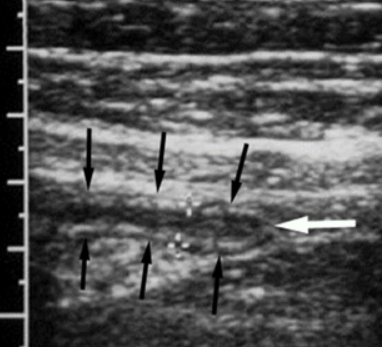

Keyboard sign